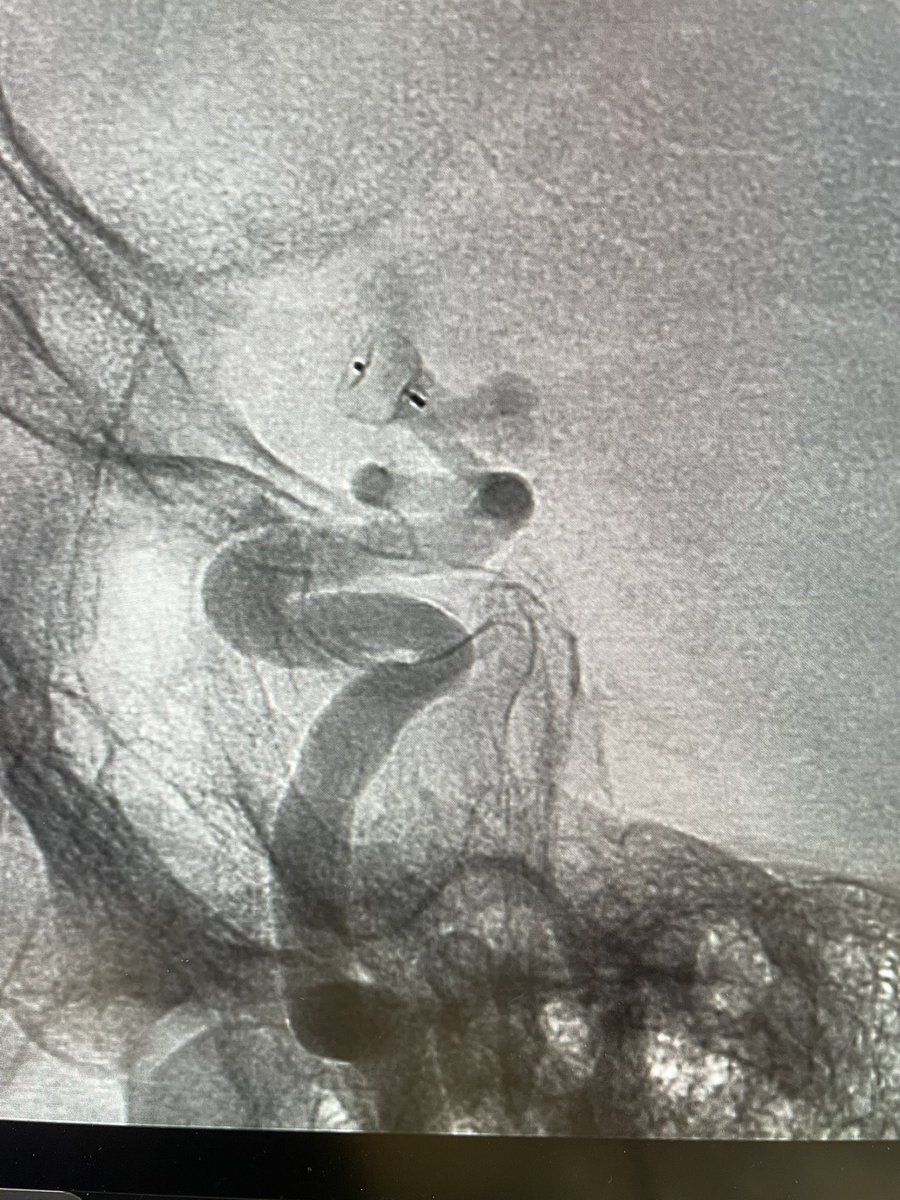

Dr. Thana Theofanis and her team at Bryn Mawr Main Line Health successfully treated this right M1 occlusion using the ERIC 4x30 device in a single pass. Thana Theofanis M.D. #ERICRetrievalDevice #neurointervention #neurovascular #thrombectomy #neurotwitter

Dr. Thana Theofanis and her team at Bryn Mawr <a href="/mainlinehealth/">Main Line Health</a> successfully treated this right M1 occlusion using the ERIC 4x30 device in a single pass.

#ERICRetrievalDevice #neurointervention #neurovascular #thrombectomy #neurotwitter